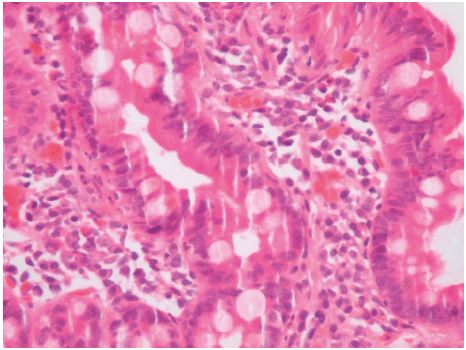

Face o resultado da TC, realiza trânsito gastro-duodenal onde se observa piloro permeável para o bolbo doudenal, que apresenta espessamento do relevo mucoso, aspeto este que se mantém em continuidade na primeira e segunda porções do duodeno, compatível com fenómenos inflamatórios. Observa-se, ainda, imagem aditiva com sinal «windsock» na 2a porção duodenal com 3,2 cm de diâmetro compatível com DDI (fig. 2) e dilatação de DII e DIII com cerca de 5,5 cm de calibre, com manutenção do relevo mucoso e conservação da distensibilidade, cuja causa localiza-se na linha média e é sugestiva de pinça aórtico-mesentérica. Efetua, também, endoscopia digestiva alta (EDA) que identifica algumas pequenas erosões agudas no antro gástrico, bulbite erosiva marcada e edema das pregas em DII condicionando estenose relativa com alguns restos alimentares impactados. Efetuadas biópsias apenas no bolbo e DII, revelando, no estudo morfológico, infiltrado inflamatório moderado da lâmina própria, constituído predominantemente por eosinófilos (cerca de 35 por CGA) sugestivo de duodenite eosinofílica (fig. 3).

Figura 3 Biópsias do duodeno com infiltrado inflamatório esosinofílico na lâmina própria. Duodenite esosinofílica (cerca de 35 eosinófilos por CGA).